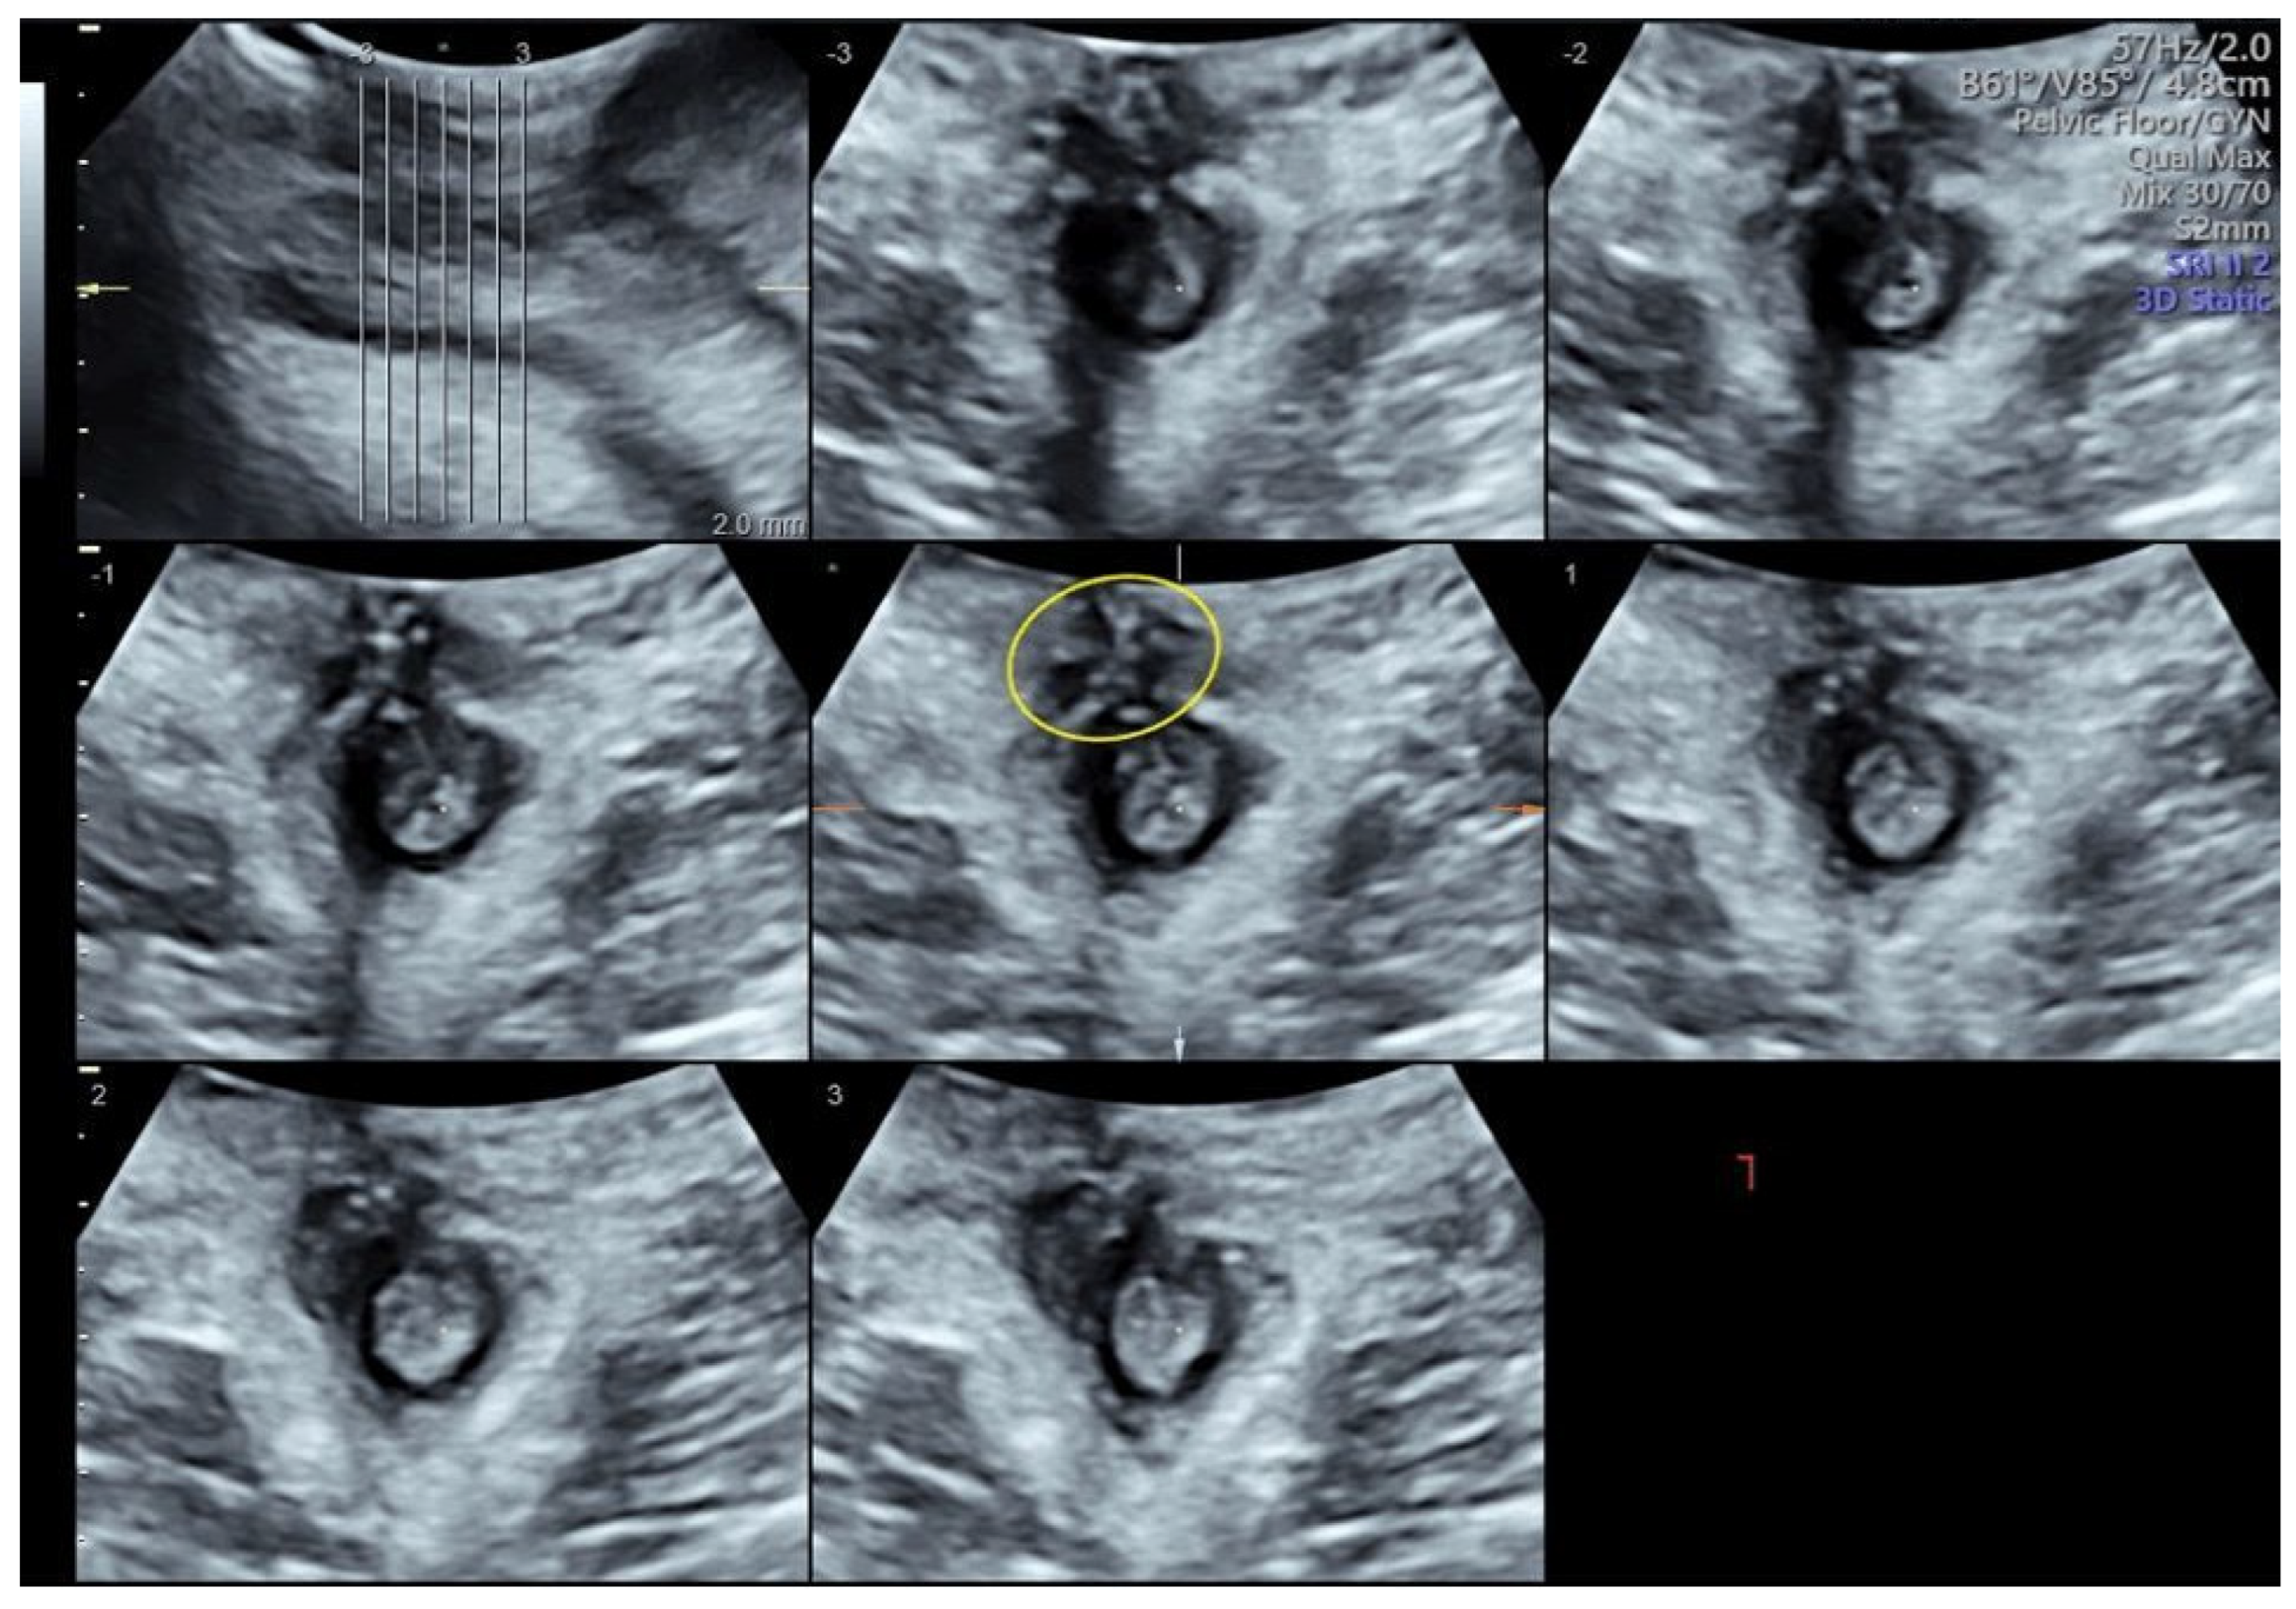

- Stickelmann, A.-L.; Kennes, L.N.; Hölscher, M.; Graef, C.; Kupec, T.; Wittenborn, J.; Stickeler, E.; Najjari, L. Obstetric Anal Sphincter Injuries (OASIS): Using Transperineal Ultrasound (TPUS) for Detecting, Visualizing and Monitoring the Healing Process. BMC Women’s Health 2022, 22, 339. [Google Scholar] [CrossRef] [PubMed]

- Ros, C.; Martínez-Franco, E.; Wozniak, M.M.; Cassado, J.; Santoro, G.A.; Elías, N.; López, M.; Palacio, M.; Wieczorek, A.P.; Espuña-Pons, M. Postpartum Two- and Three-Dimensional Ultrasound Evaluation of Anal Sphincter Complex in Women with Obstetric Anal Sphincter Injury. Ultrasound Obs. Gynecol. 2017, 49, 508–514. [Google Scholar] [CrossRef]

- Hakim, S.; Santoso, B.I.; Djusad, S.; Moegni, F.; Surya, R.; Kurniawan, A.P. Diagnostic Capabilities of Transperineal Ultrasound (TPUS) to Evaluate Anal Sphincter Defect Post Obstetric Anal Sphincter Injury (OASIS)? A Systematic Review. J. Ultrasound 2023, 26, 393–399. [Google Scholar] [CrossRef]

- Volløyhaug, I.; Taithongchai, A.; Arendsen, L.; Van Gruting, I.; Sultan, A.H.; Thakar, R. Is Endoanal, Introital or Transperineal Ultrasound Diagnosis of Sphincter Defects More Strongly Associated with Anal Incontinence? Int. Urogynecol. J. 2020, 31, 1471–1478. [Google Scholar] [CrossRef]

- Barbosa, M.; Christensen, P.; Møller-Bek, K.; Brogaard, L.; Glavind-Kristensen, M. Can Ultrasound 10 Days after Obstetric Anal Sphincter Injury Predict Anal Incontinence at Long-Term Follow-Up? Int. Urogynecol. J. 2021, 32, 2511–2520. [Google Scholar] [CrossRef]

- Abdool, Z.; Sultan, A.H.; Thakar, R. Ultrasound Imaging of the Anal Sphincter Complex: A Review. BJR 2012, 85, 865–875. [Google Scholar] [CrossRef]

- García-Mejido, J.A.; Gutiérrez Palomino, L.; Fernández Palacín, A.; Sainz-Bueno, J.A. Aplicabilidad de la ecografía transperineal en 3/4D para el diagnóstico de lesiones del esfínter anal durante el posparto inmediato [Applicability of 3/4D transperineal ultrasound for the diagnosis of anal sphincter injury during the immediate pospartum]. Cir. Cir. 2017, 85, 80–86. [Google Scholar] [CrossRef]